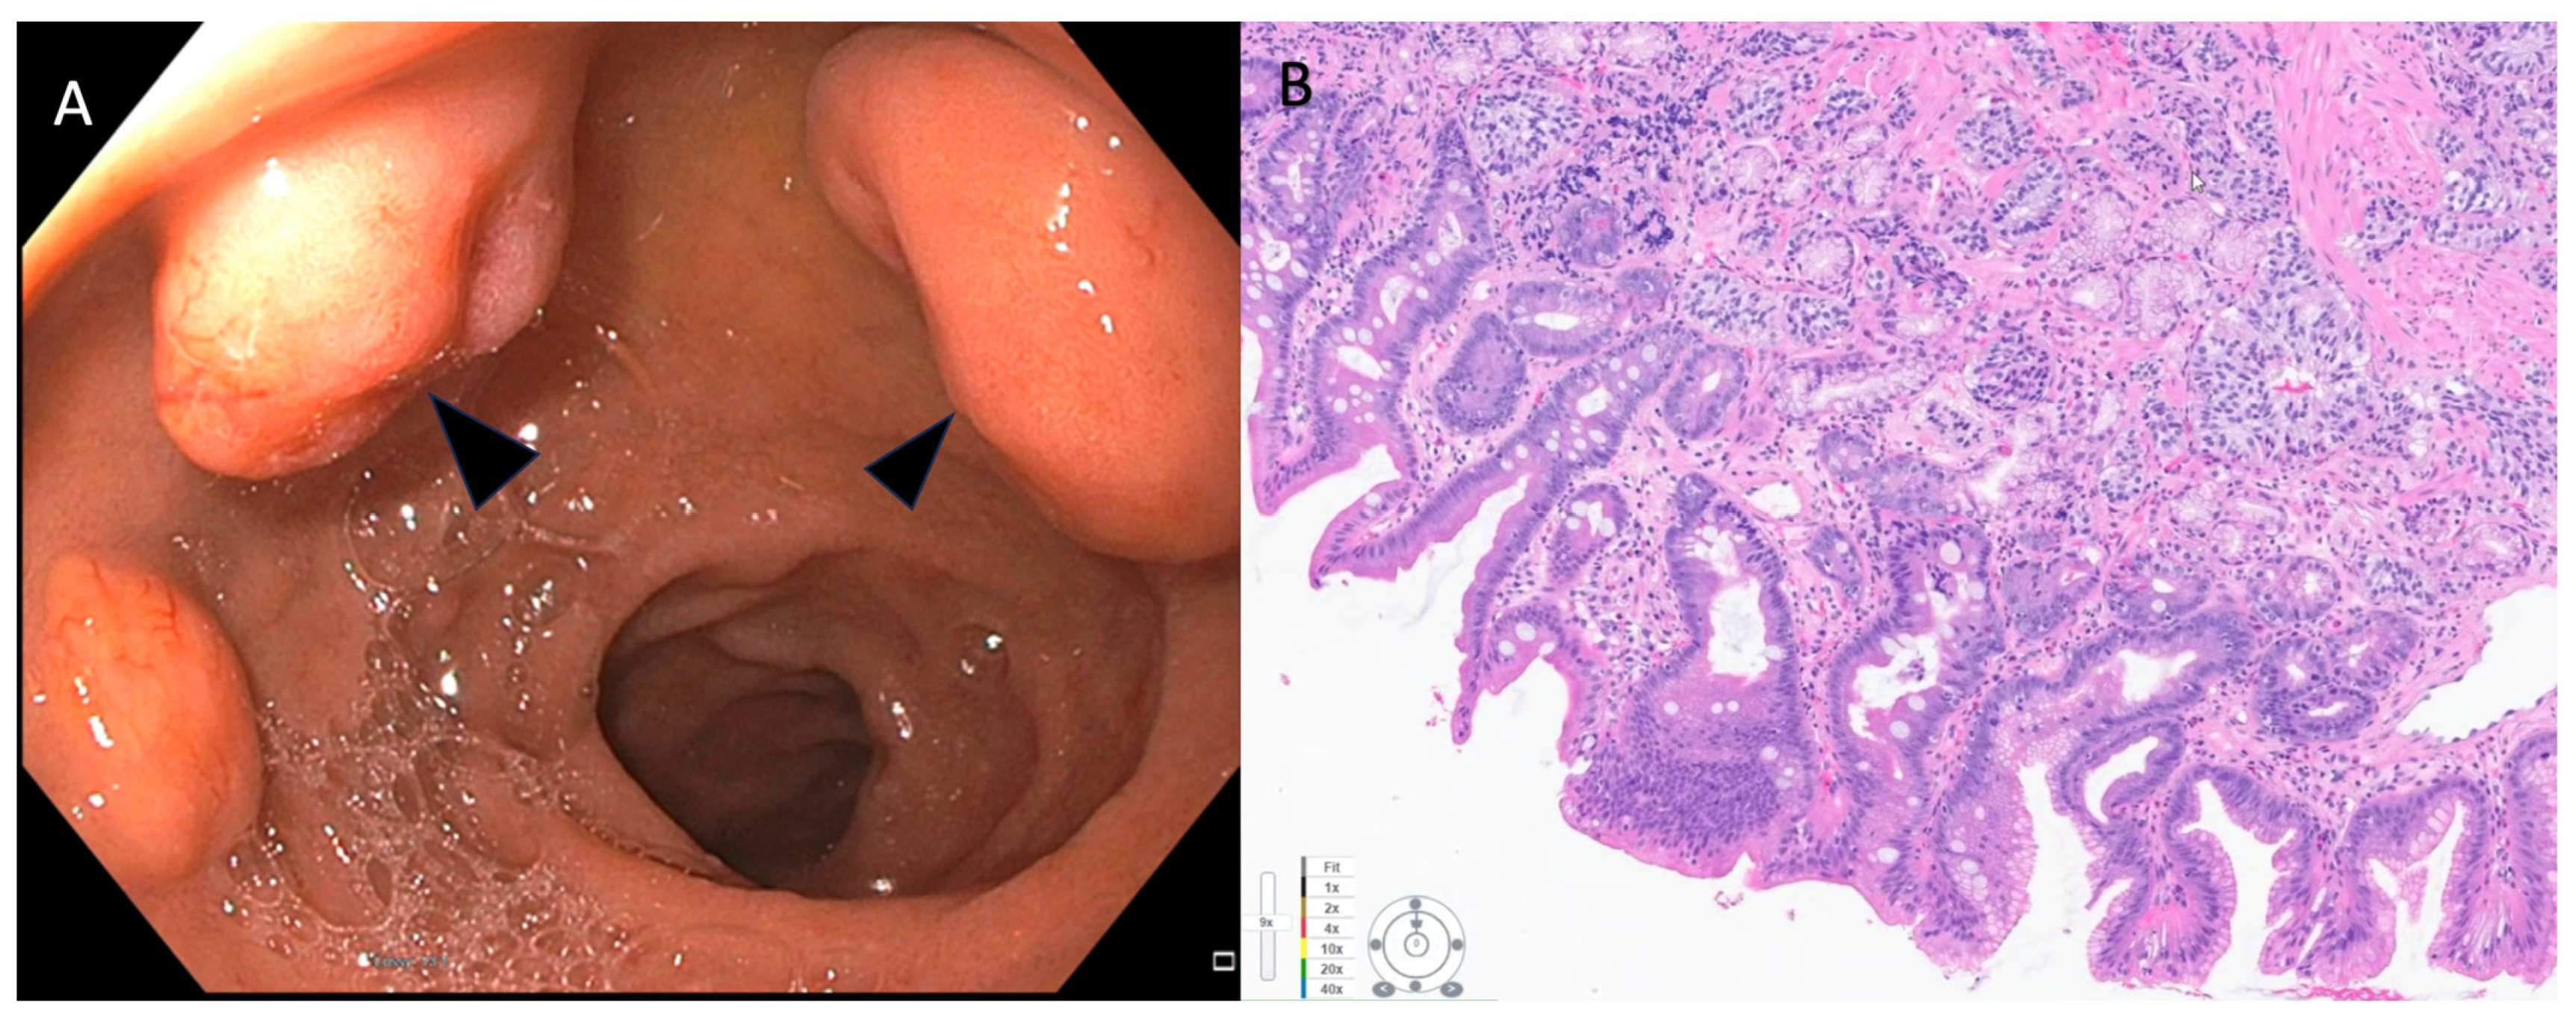

- Veyre, F.; Lambin, T.; Fine, C.; Fenouil, T.; Rostain, F.; Walter, T.; Pioche, M. Endoscopic characterization of rectal neuroendocrine tumors with virtual chromoendoscopy: Differences between benign and malignant lesions. Endoscopy 2021, 53, E215–E216. [Google Scholar] [CrossRef]